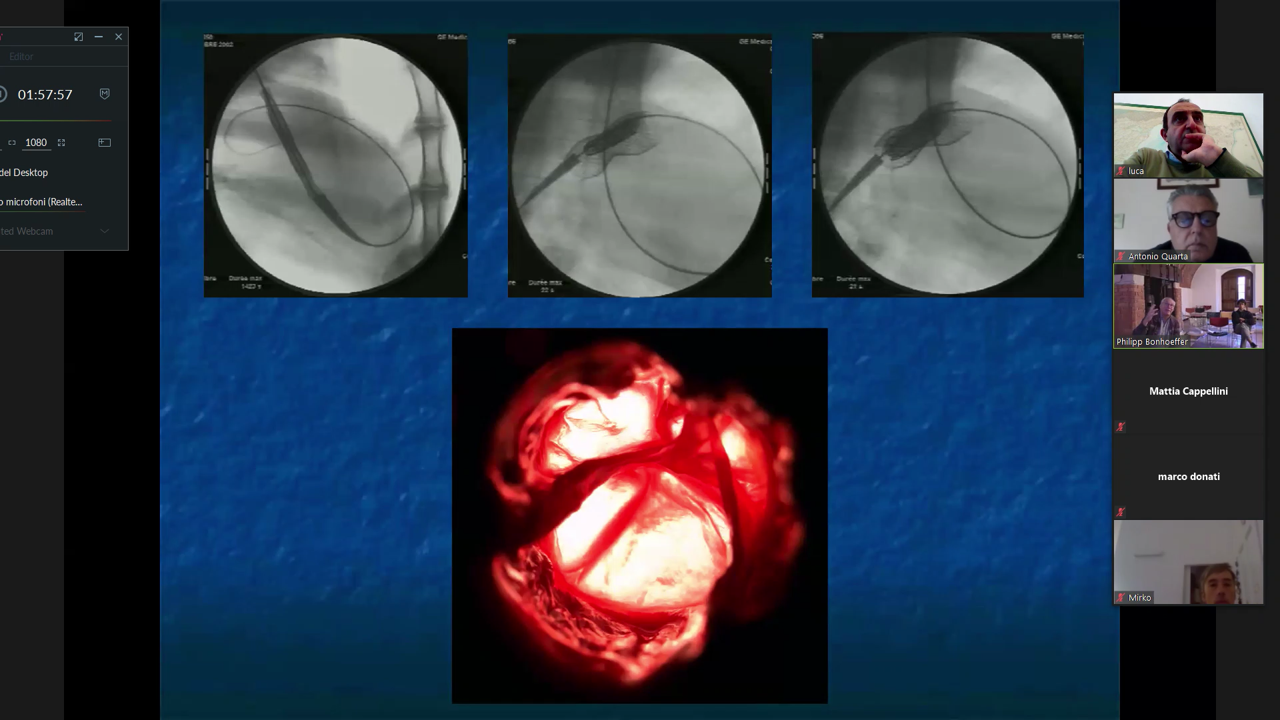

Negli anni mette a punto altre tecniche interventistiche tra le quali la rivoluzionaria procedura non invasiva che permette di inserire una valvola ricavata dalla giugulare bovina nell’arteria polmonare senza ricorrere all’intervento chirurgico a cuore aperto (valvola Melody).

Il dott. Bonhoeffer ha fatto ben capire l’importanza della multidisciplinarità ponendo particolarmente attenzione ai materiali e alle tecnologie; in particolare ha illustrando la parte di modellazione 3D, l’analisi ad elementi finiti ed in ultimo la realizzazione delle parti mediante la stampante 3D, tecnologie che oggi ragazzi hanno a disposizione anche a scuola ma che lui aveva iniziato ad utilizzare già nel 2004 con il team specialistico formato prevalentemente da ingegneri.

La ricerca infatti non finisce mai, ed in collaborazione con una équipe multidisciplinare, composta da di cardiologi, radiologi, cardiochirurghi, ingegneri biomedici ed una ditta, ha sviluppato e progettato una seconda generazione di valvola che ha permesso di trattare un maggior numero di pazienti.

Il primo impianto nell’uomo al mondo è stato fatto nel 2009.